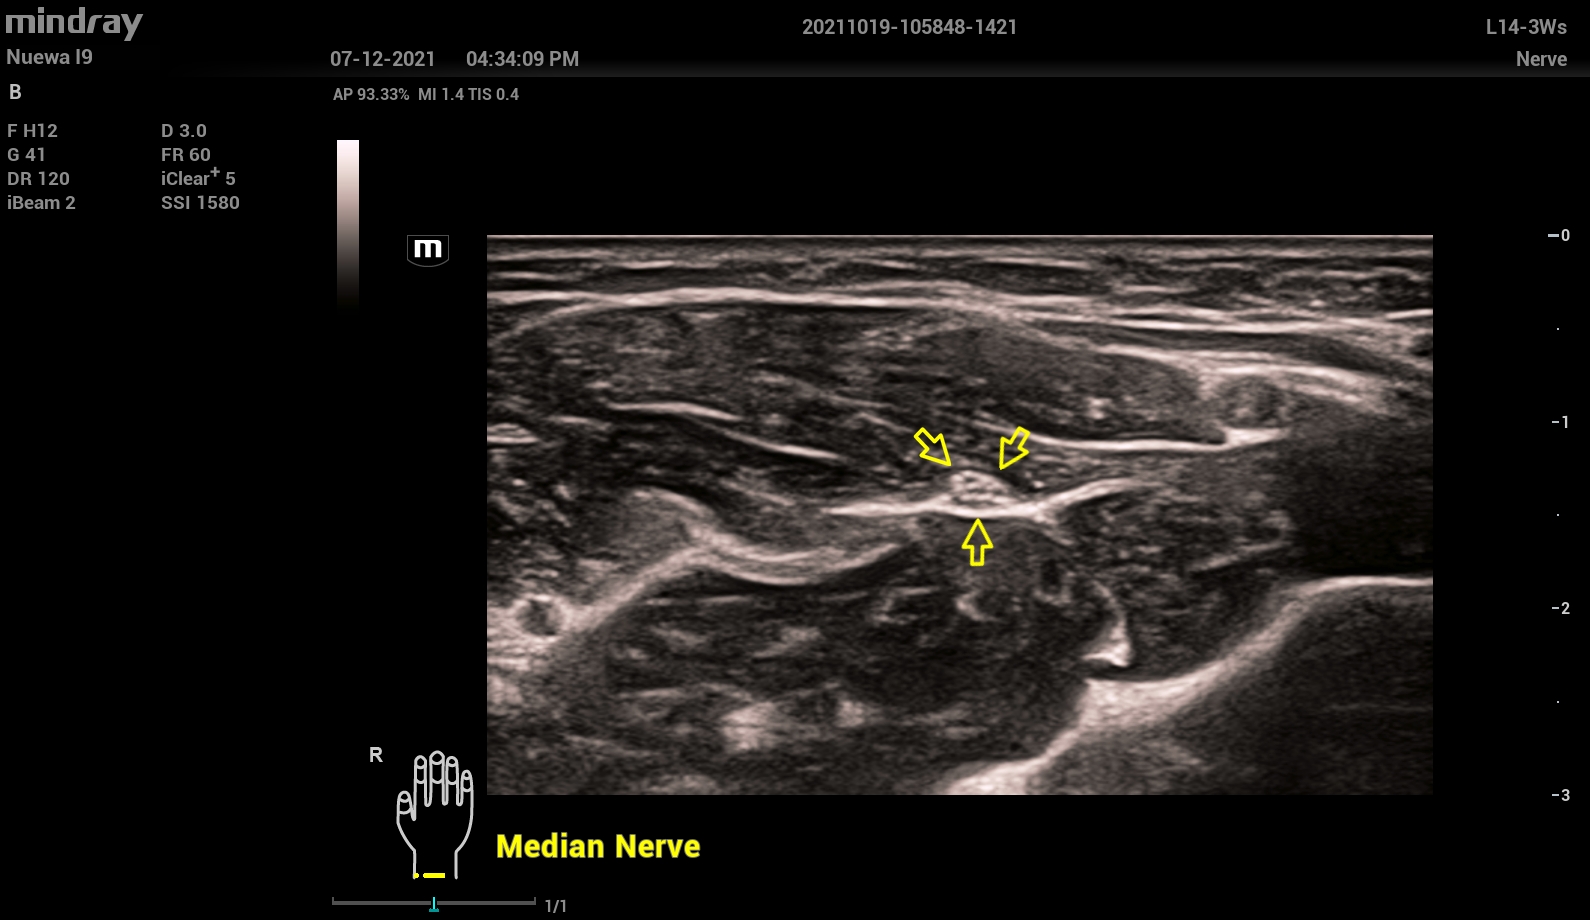

-Блокады нервов и регионарной анестезии (Nerve Package)